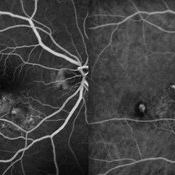

Best Disease Best DiseaseMar 9 2013 by Hamid Ahmadieh, MD FA and ICG Angiography of the left eye of a 49-year-old man with advanced Best disease. Photographer: Soodabeh Fooladin, Negah Eye Center, Tehran Imaging device: Heidelberg Spectralis Condition/keywords: Best disease, indocyanine green (ICG) angiography